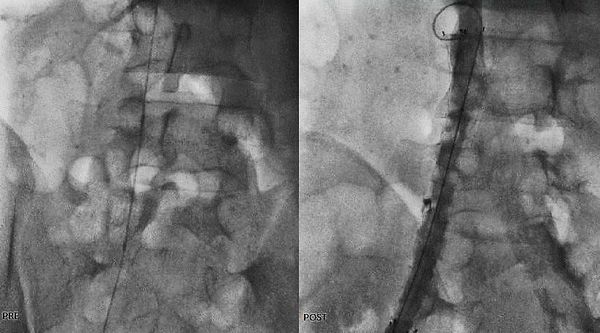

استشاري جراحة الأوعية الدموية و القسطرة التداخلية الطرفية